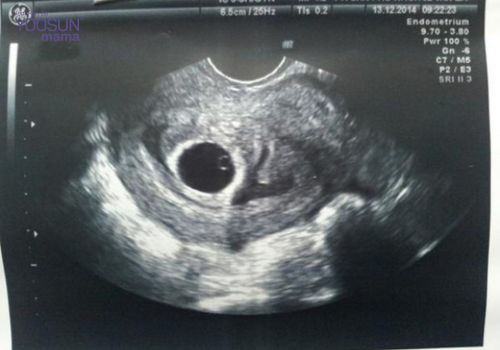

Thông thường, sau khi phụ nữ mang thai khoảng 5 hoặc 6 tuần trứng đã thụ tinh sẽ có phôi thai và túi thai rộng khoảng 18mm. Đối với trường hợp thai trứng trống, túi thai vẫn hình thành và phát triển nhưng không có phôi thai.

Phát hiện mang thai trống chỉ được xác định thông qua siêu âm. Hình ảnh siêu âm sẽ phản ánh một cách chính xác nhất tình trạng túi thai rỗng. Vì vậy, khi phát hiện có bất kỳ dấu hiệu bất thường nào chị em nên đến gặp ngay bác sĩ để được thăm khám.